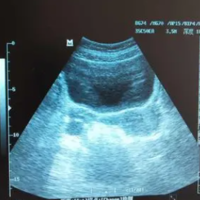

备孕是一件非常重要的事情,很多准备要孩子的夫妻都非常关心如何提高成功率。卵泡监测是备孕过程中非常常见的一种方法。但是,备孕有必要监测卵泡吗?下面我们来详细讨论一下。什么是卵泡监测卵泡监测是通过超声波或其他诊断手段,及时观察女性卵巢里的卵泡发育状况,判断卵泡大小、数量、位置、形态等指标,以便确定排卵期和最佳受孕时机。卵泡监测有哪些方法目前比较常用的卵泡监测方法有以下几种:经腹超声检查 、经阴道超声检

备孕是一件非常重要的事情,很多准备要孩子的夫妻都非常关心如何提高成功率。卵泡监测是备孕过程中非常常见的一种方法。但是,备孕有必要监测卵泡吗?下面我们来详细讨论一下。什么是卵泡监测卵泡监测是通过超声波或其他诊断手段,及时观察女性卵巢里的卵泡发育状况,判断卵泡大小、数量、位置、形态等指标,以便确定排卵期和最佳受孕时机。卵泡监测有哪些方法目前比较常用的卵泡监测方法有以下几种:经腹超声检查 、经阴道超声检

做b超监测卵巢卵泡之前需要健康饮食、注意检测时间、注意局部卫生。通过卵泡监测最能客观反映卵泡生长发育状况,观察是否有排卵,并同步反映子宫内膜的发育状况。在做卵泡监测前需要注意局部卫生,保持局部卫生的情节,还要保持良好的生活习惯,包括健康饮食、充足睡眠和适量运动,以确保身体处于最佳状态,还要注意监测时间,月经规律和不规律的女性监测时间不同。监测卵泡这种检查看起来比较麻烦,但非常重要,具有重要的临床意

“卵巢”最主要的功能是产生“卵子”,好的卵子可以为优生优育提供基础,那要怎么才能知道自己的卵子好不好呢?其实可以通过观察卵泡来推测卵子的发育情况,那医院监测卵泡是怎么监测的?监测之前需要憋尿吗?医院测卵泡怎么测卵泡检查不是每个备孕的女性都要做的。对于备孕的女性来说,最好是夫妻先一同去医院做一下孕前检查,这其中包括了男性的精液检查,如果很好,女性就从月经当天算起,到月经结束后的7天,再去做相应的检查

关于排卵监测,之前的文章也讲到过,有基础测体温法、排卵试纸监测法、看阴道分泌物、排卵痛疼痛法等。今天我们要说的是B超监测排卵法,这是观察卵泡发育、内膜厚度和确定排卵期最准确的方法。卵泡怎么检查卵泡对于女性的生育能力有特别大的影响,要是卵泡不良的话,就很容易使女性不孕。如果因为卵泡问题而影响到了生育的时候,就需要对卵泡进行检查、检测了,然后才能针对性的进行治疗。女性进行卵泡检查时,最常采用的就是通过